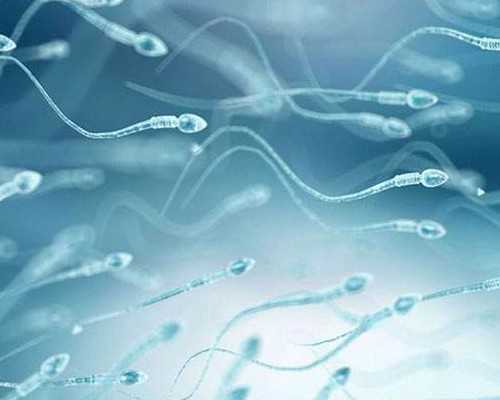

2、明確精液情況:檢查男方是否有足量、健康符合生育要求的精子,了解精子的數量和活動度等。如果精子正常,無需繼續檢查。如果精液質量異常,需要繼續查明原因,例如B超、性激素、染色體等,具體要根據醫生安排進行。